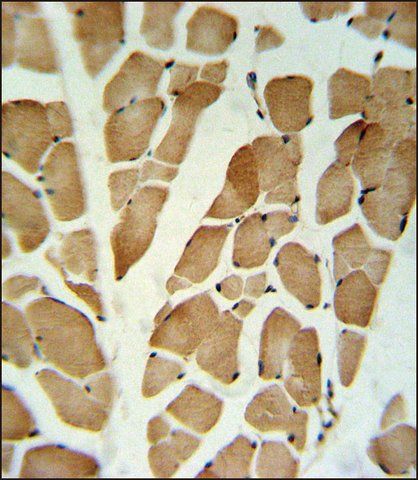

The Human Protein Atlas project can be subdivided into three efforts: Human Tissue Atlas, Cancer Atlas, and Human Cell Atlas. The antibodies that have been generated in support of the Tissue and Cancer Atlas projects have been tested by immunohistochemistry against hundreds of normal and disease tissues and through the recent efforts of the Human Cell Atlas project, many have been characterized by immunofluorescence to map the human proteome not only at the tissue level but now at the subcellular level. These images and the collection of this vast data set can be viewed on the Human Protein Atlas (HPA) site by clicking on the Image Gallery link. To view these protocols and other useful information about Prestige Antibodies and the HPA, visit sigma.com/prestige.

| technique(s) | immunohistochemistry: 1:20- 1:50 |